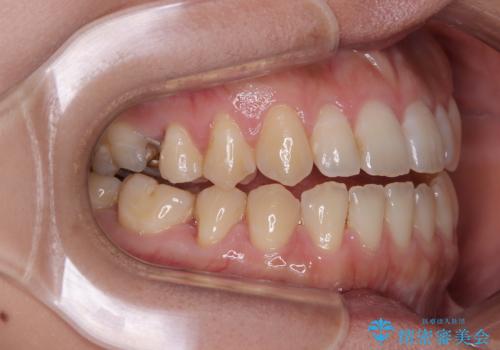

【モニター】食事が取りづらい 極端な開咬をインビザラインで解決

- 極端な開咬を気にして来院された患者様です。

開咬の方の特徴として、幼少期の指しゃぶりの癖や、強い舌の突出癖が挙げられます。

こちらの患者様も強い舌の突出癖が認められたため、矯正治療を行うにあたり、舌のトレーニングをしっかりと行っていただくように指示をいたしました。

開咬はインビザラインが得意とする歯列不正であるため、舌のトレーニングを行いながら、インビザラインにて矯正治療を行うこととしました。

担当医としては、もっと上下の前歯を接触させるところまで治療を進めたいという思いがありますが、今まで咀嚼できなかったものが食べられるようになったということで、この状態で治療終了となりました。